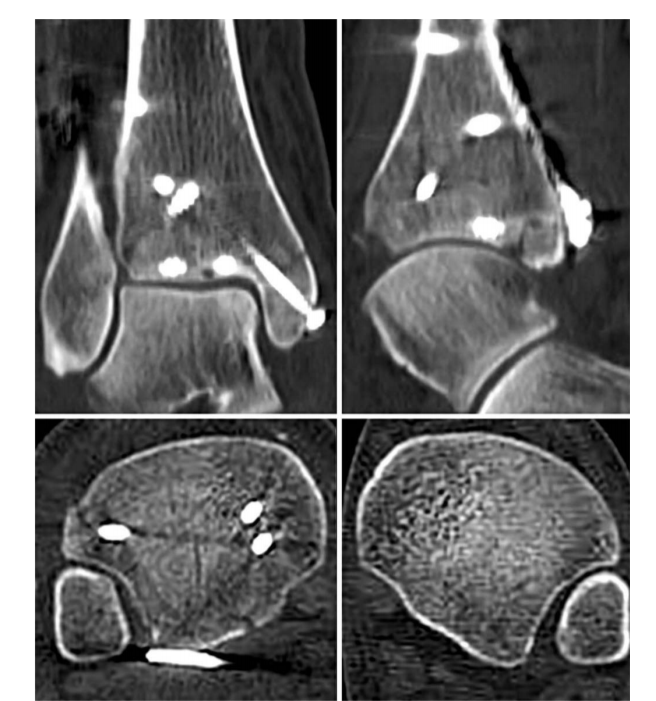

③首先俯卧位后外侧入路固定后踝,存在夹层骨块可行克氏针临时固定后抗滑钢板固定后踝。

④ 固定后踝后,经同一后外侧切口固定外踝,通常建议采用后侧钢板固定,如腓骨骨折线过高,则重新切口外侧钢板固定腓骨。

⑤ 内踝常规切口固定内踝。

⑥俯卧位患者屈曲膝关节,经前外侧切口固定前踝骨折块,通常选用2.7mm或3.5mm螺钉,并使用垫圈。

⑦ 固定后常规检查下胫腓联合稳定性。

⑧ 复位后典型病例示意图。